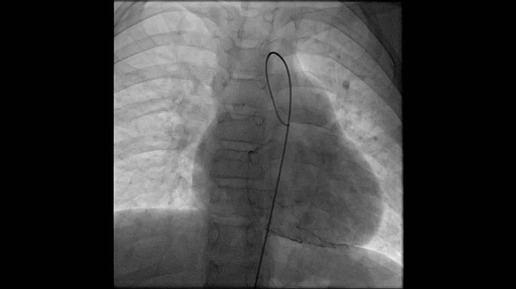

04:291,0×00:00/04:29Репротезирование клапансодержащего гомографта лёгочной артерии после перенесённого бактериального эндокардита5 месяцев назад